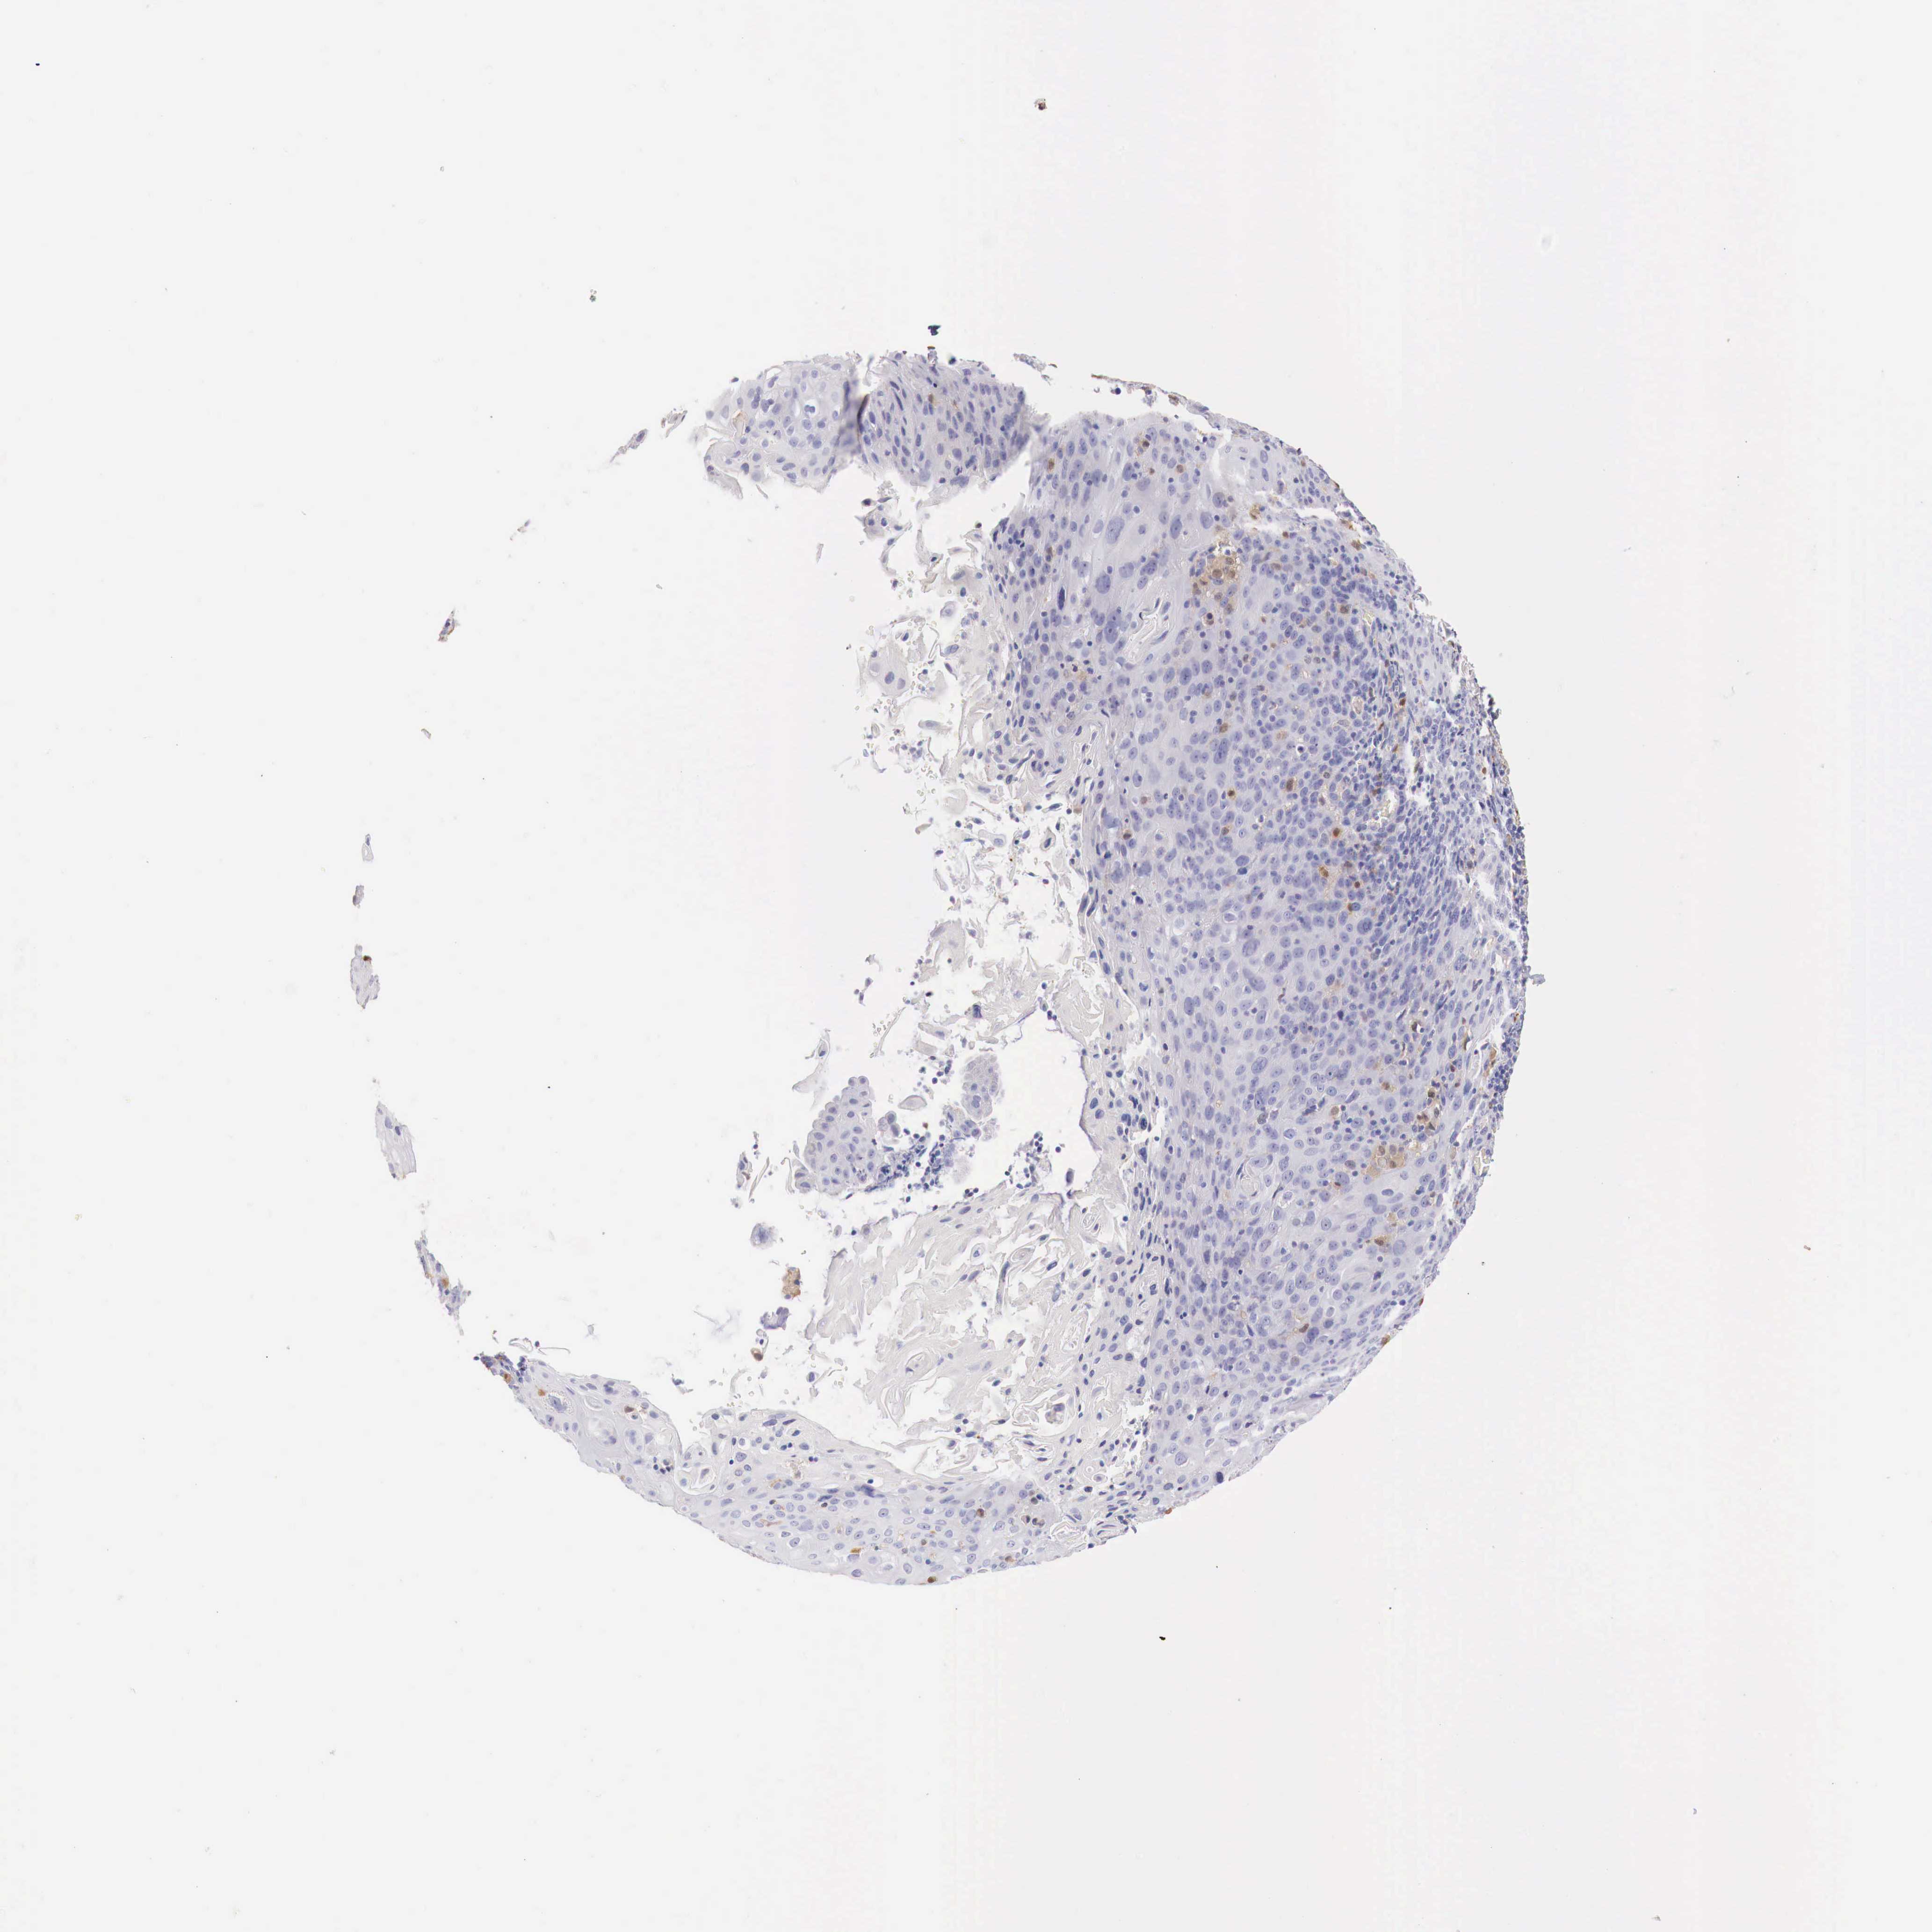

CERVICAL CANCER - Protein expressioni

A mouse-over function shows sample information and annotation data. Click on an image to view it in a full screen mode. Samples can be filtered based on level of antibody staining by selecting one or several of the following categories: high, medium, low and not detected. The assay and annotation is described here.

Note that samples used for immunohistochemistry by the Human Protein Atlas do not correspond to samples in the TCGA dataset.

Antibody stainingi

Antibody staining in the annotated cell types in the current human tissue is reported as not detected, low, medium, or high, based on conventional immunohistochemistry profiling in selected tissues. This score is based on the combination of the staining intensity and fraction of stained cells.

Each image is clickable and will lead to virtual microscopy that enables deeper exploration of all samples and also displays staining intensity scores, fraction scores and subcellular localization as well as patient and tissue information for each sample.

Antibody HPA000428

Antibody HPA000522

Staining

High

Medium

Low

Not detected

Intensity

Strong

Moderate

Weak

Negative

Quantity

>75%

75%-25%

<25%

None

Location

Nuclear

Cytoplasmic/membranous

Cytoplasmic/membranous,nuclear

Adenocarcinoma, NOS

Squamous cell carcinoma, NOS